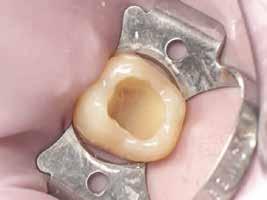

Belső gyökérfelszívódás egy ülésben

történő ellátása endodonciai és sebészi terápia együttes alkalmazásával

Belső gyökérfelszívódás (internal root resorbtion; IRR) esetében a gyökeret alkotó kemény szövetek odontoclastok által történő lebontását figyelhetjük meg. Ez a legtöbb esetben egy teljesen tünetmentes ismeretlen etiológiájú folyamat. A belső gyökérfelszívódást legtöbbször accidentális leletként más, panaszokat okozó fogakról készült röntgenfelvételeken vagy tájékozódási céllal készített panorámafelvételeken diagnosztizálhatjuk. Gyanú esetén kifejezetten ajánlott CBCT-felvétel készítése, amely sokkal egyértelműbbé teszi az IRR fennállását, valamint nagymértékben elősegíti a kezelés megtervezését. Az IRR két különböző formában jelentkezhet: gyulladásos vagy helyettesítő reszorbció. Az előbbi általában kerekded, szabályos léziót okoz, míg az utóbbi megjelenésében a külső cervikális reszorbció képét utánozza. Ennek megfelelően ezt nagyobb eséllyel diagnosztizálják félre. A belső gyökérfelszívódás ellátása során a legfontosabb a még vitális pulpaszövetek teljes körű eltávolítása, ugyanis ez tartja fenn a reszorbtív folyamatot. Ha a destruktív folyamat még nem törte át a gyökér külső falát, akkor elegendő a fog gyökérkezelése, azonban ha a gyökér már perforálódott, akkor a legtöbbször sebészi kiegészítő

terápia alkalmazása is szükségessé válik.

Első esetbemutatás

A 40 éves hölgypácienst a bal felső nagymetszőfogában accidentálisan diagnosztizált IRR kezelése céljából irányították rendelőnkbe.

Az elváltozást egy diagnosztikai céllal készített panoráma-röntgenfelvételen észlelték. Az elváltozás kiterjedésének pontos meghatározása, valamint a kezelési terv felállításának és a várható prognózis megítélésének elősegítése érdekében CBCT-felvétel készült (1. a–c ábra). A reszorbtív lézió a fog gyökerének középső harmadában helyezkedett el és a

gyökér meziális felszínét perforálta. A lézió kerek és szimmetrikus volt, amely gyulladásos típusra utalt. Az oszteolitikus terület fókusza a perforáció közelében helyezkedett el (2. ábra). A csontban lévő lézió és a gyökérperforáció az endodonciai kezelés sebészi kiegészítését tette szükségessé. Ennek megfelelően az egy ülésben történő gyökérkezelést követően